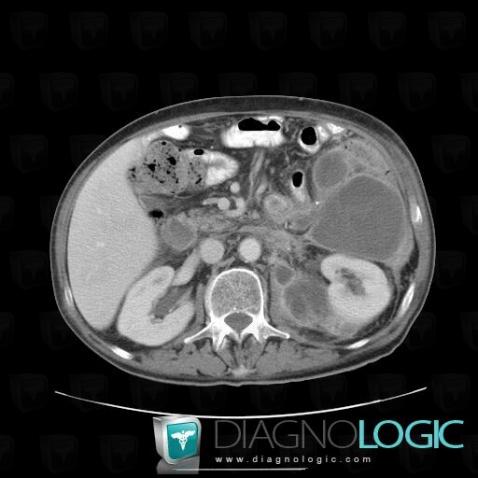

Abscess, Retroperitoneum, CT

Here is the specific information in the key image above:

- Diagnosis Abscess, Location(s) Retroperitoneum, with gamuts Lesion in the perinephric space